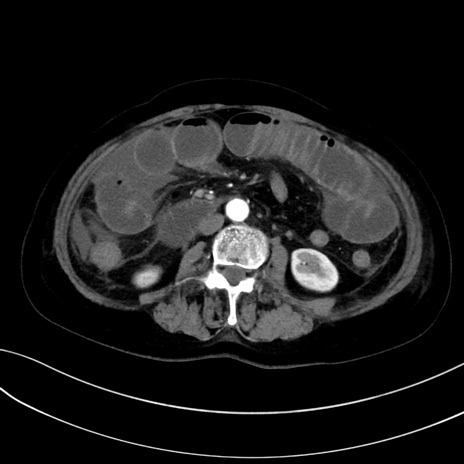

症例13 CT(横断像)1日半後